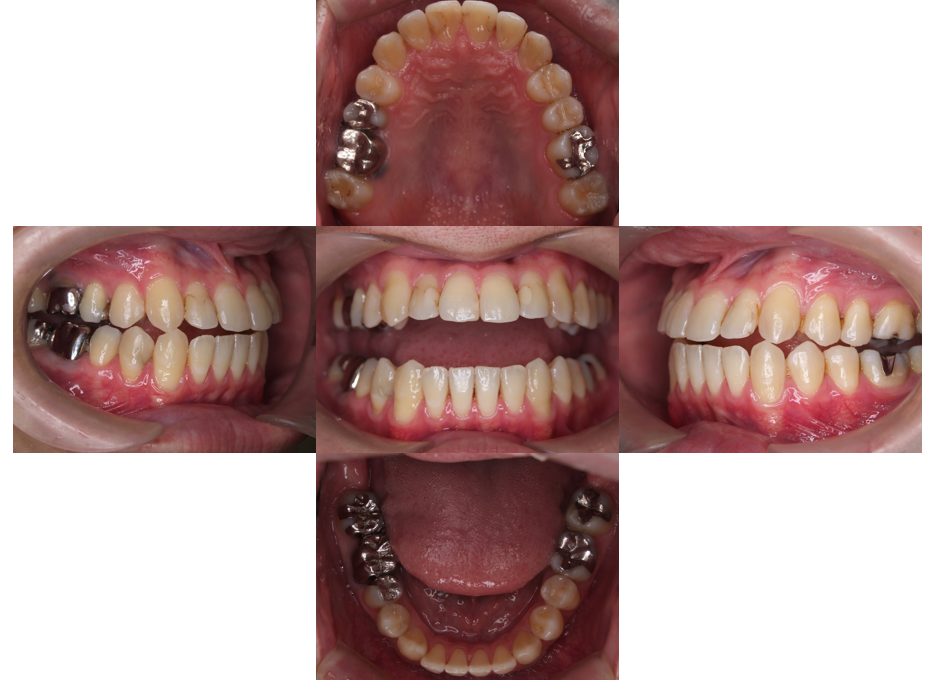

矯正治療・根管治療・補綴治療の症例紹介(三隅歯科クリニック)

三隅 賢祐(三隅歯科クリニック)

症例詳細

| 主訴 | 過去作成した右下の被せ物がずれて入っており、たまに腫れる。歯並びも気になる。 |

| 治療内容 | 矯正治療を行いました。 |

| 治療費 | 800,000円(税込み) |

| 治療期間 | 2年半(矯正治療期間 2年) |

| 治療回数 | 30回 |

| 想定されたリスク | 術前に基礎資料を整え分析し、セットアップモデル等でシミュレーションをしておかないと、予定通りの治療が行えないリスクがあった。 |